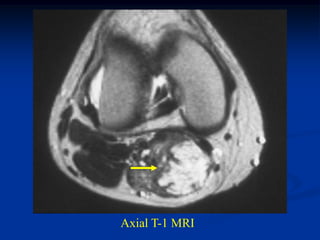

Case #270.2 Axial T-1 T-2 Gad 56 year male with painless soft mass in anterior thigh for 2 years

• 26.

Sag T-1 T-2 FS